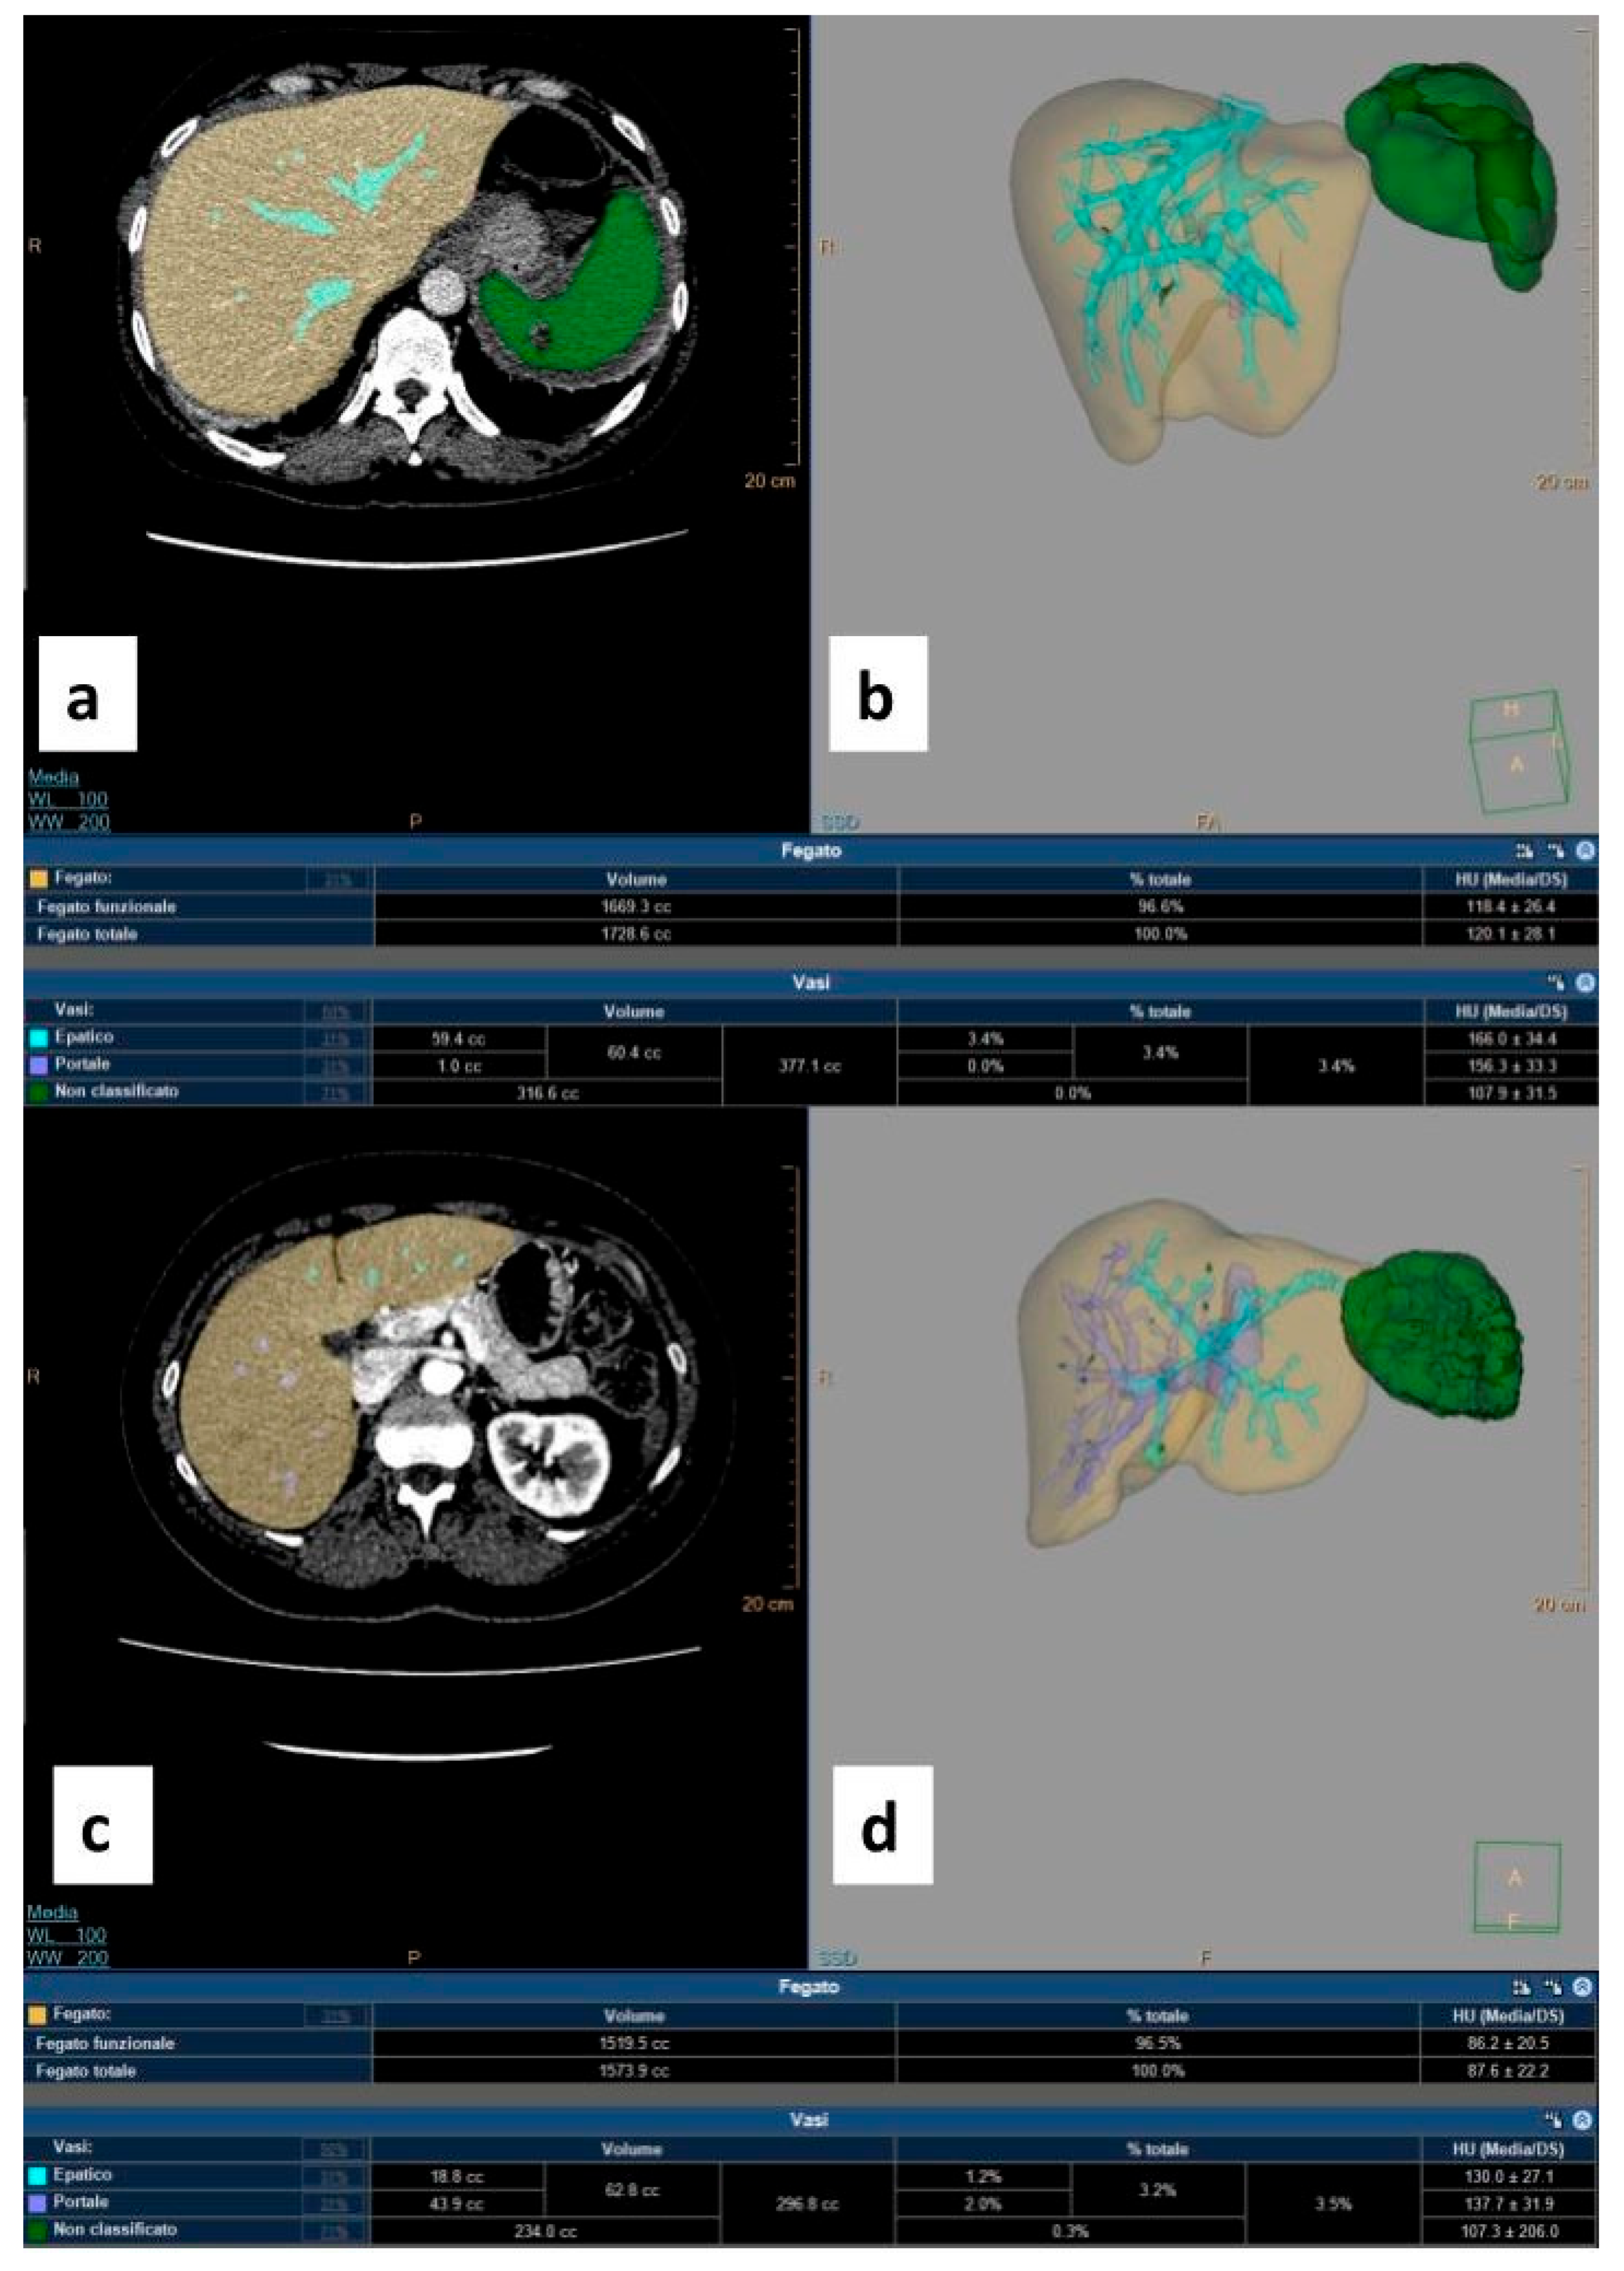

2.4. Imaging and Volumetric Analysis